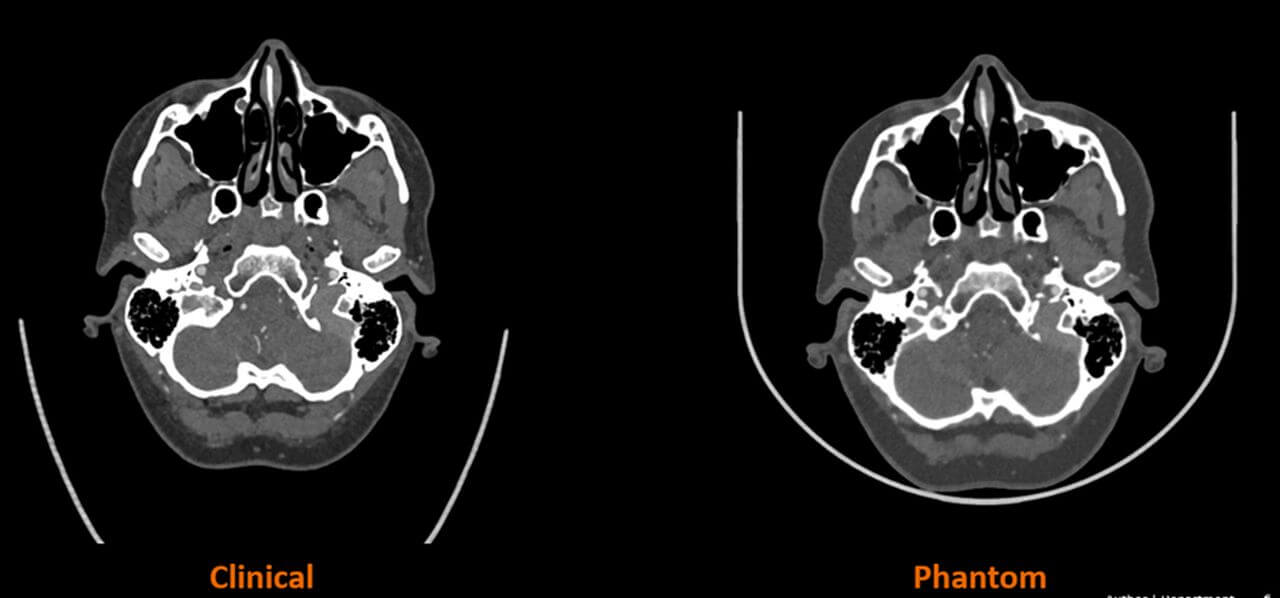

CT-Phantome sind spezialisierte Geräte, die weltweit in Krankenhäusern eingesetzt werden, um die Leistung von CT-Scannern zu bewerten und sicherzustellen. Sie simulieren bestimmte Merkmale des menschlichen Körpers und ermöglichen die Beurteilung verschiedener Kernmetriken, darunter Strahlendosis und Bildqualität. Diese Entwicklung nutzt Stratasys‘ PolyJet™-Technologie in Kombination mit seiner einzigartigen RadioMatrix™-Technologie und dem fortschrittlichen Algorithmus von Siemens Healthineers, um gescannte Patientenbilder in spezifische Materialeigenschaften mit der Radiopazität der menschlichen Anatomie zu übersetzen. Die Lösung wird eine maßgeschneiderte Herstellung von Phantomen und die Erstellung von ultra-realistischen Merkmalen der menschlichen Anatomie mit vollständiger radiographischer Genauigkeit der patientenspezifischen Pathologie ermöglichen, was zuvor nicht möglich war.

Die Forschung beginnt mit der Herstellung von 3D-gedruckten Phantomen für kleinere anatomische Strukturen wie Kopf und Hals und wird sich auf die Herstellung von zunehmend größeren und komplexeren Anatomien erstrecken, bis hin zum Phase-One-Endpunkt des 3D-Drucks eines Herzmodells und eines gesamten menschlichen Torsos mit vollständiger radiographischer Genauigkeit.